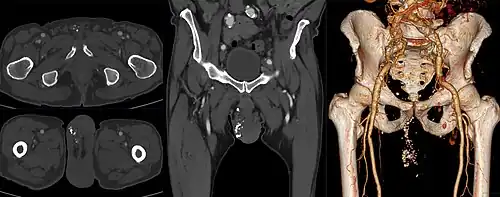

A phlebolith is a small local, usually rounded, calcification within a vein. These are very common in the veins of the lower part of the pelvis, and they are generally of no clinical importance. When located in the pelvis they are sometimes difficult to differentiate from kidney stones in the ureters on X-ray.[1]

Phleboliths in the pelvic region are present in about 44.2% of people and are more common in females (50.1%) than males (37.3%). The amount of phleboliths increases with age and they also appear more often on the left than on the right side of the pelvic region.[2] Phleboliths outside the pelvic region appear in about 2% of the population.[3]